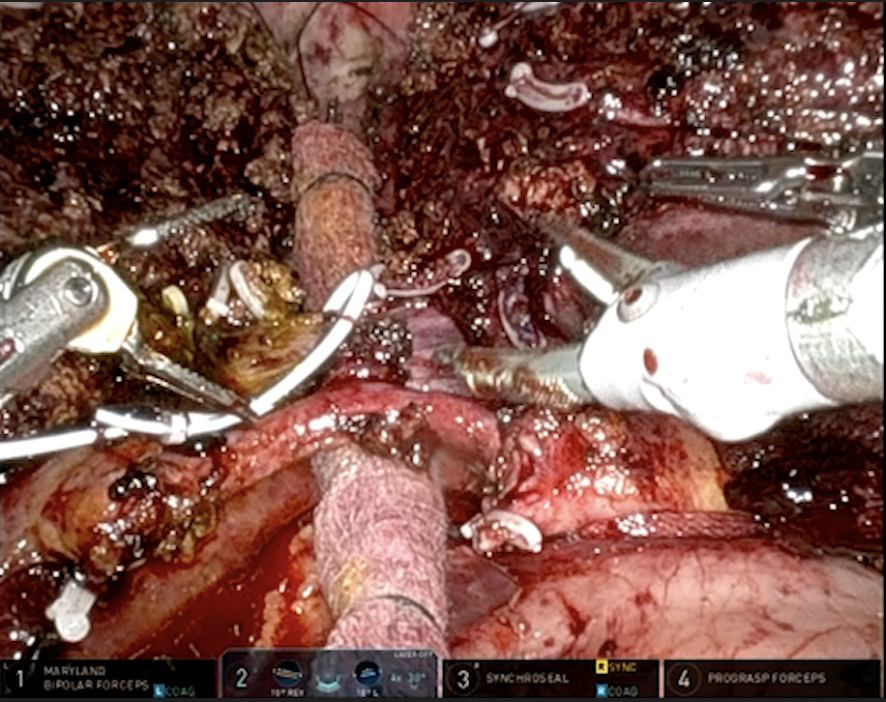

Completed another robotic donor right hepatectomy with @BenSamstein. This time we invited @JHawksworthMD to maximize our 🤖LD experience on both campuses. 👉 https://t.co/wL9GLYyVe9 (different case) @WCMSurgery @ColumbiaSurgery @ILLS_LAPLIVER @ASTSChimera